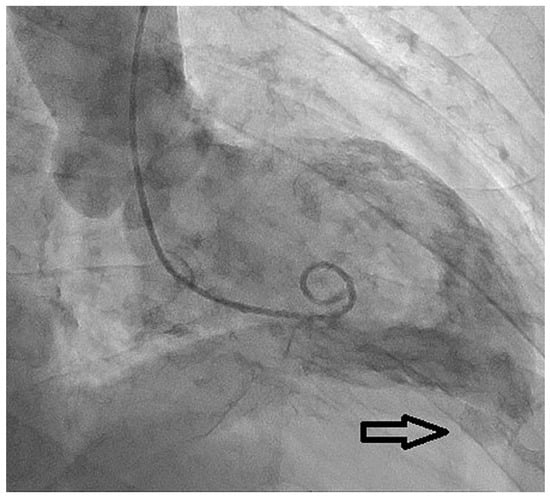

The coronary angiogram showed chronic total occlusion of the mid-right coronary artery, which was not treated as there was only slight ischaemia on scintigraphy and large epicardial collaterals from the left anterior descending artery (LAD). An intermediate lesion on the LAD was not haemodynamically significant after instantaneous wave-free ratio measurement (IFR 0.94). Left ventriculography confirmed the presence of an apical lesion compatible with a left ventricular diverticulum (Figure 3).

Figure 3. Left ventriculogram: the examination showed the presence of a left ventricular apical diverticular excrescence (black arrow) without interventricular communication.